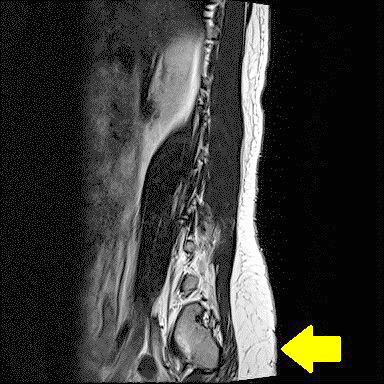

核磁共振檢查出隱性脊柱裂的病灶。圖/台北慈濟醫院

兒童以非侵入性檢查優先

核磁共振是現今脊柱裂的檢查中最能準確診斷的工具,因此當臨床懷疑孩子患病,就會安排檢查。但是顯性、隱性兩種病症的表現不同,所以檢查方式也有差異。就隱性脊柱裂患者來說,從非侵入性的尿流速、膀胱餘尿量到侵入性的錄影尿動力學來確認病人膀胱神經受損程度,並同時運用超音波或X 光確定便祕情形。

要是大一點、可以溝通的兒童來到門診,醫師會請他在尿流速儀器上尿尿,藉此觀察小便流速;正常尿流速為一秒鐘大於等於二十五毫升,但若兒童的尿速度不到五毫升,餘尿又多,就會高度懷疑是脊柱裂,進一步安排錄影尿動力學。待確診後,才會做核磁共振確認病灶位置,進行治療。